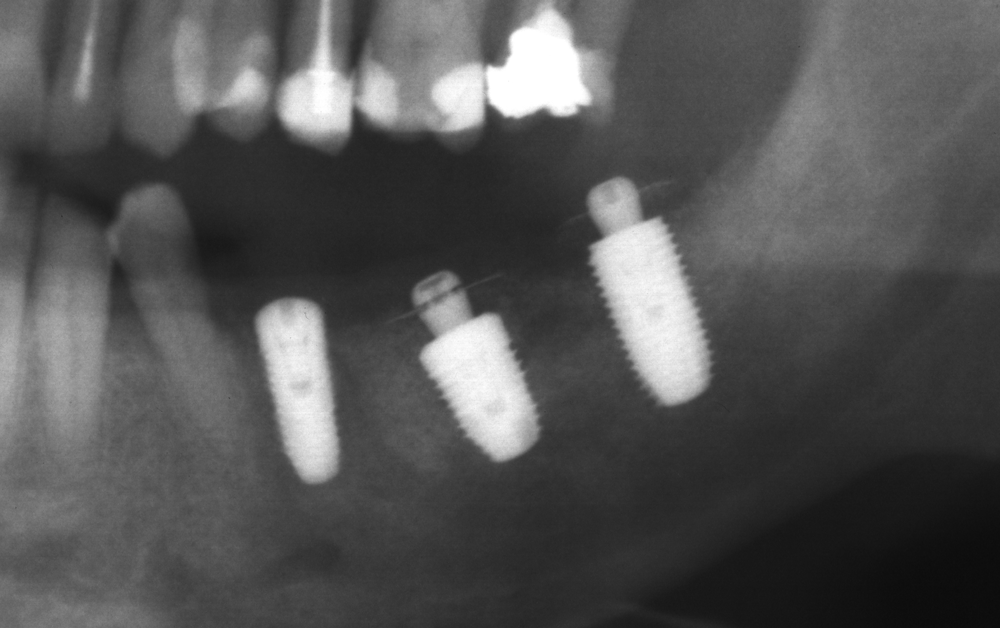

Титановите мембрани са твърди, ригидни приспособления, които се поставят в участъци с необходимост от увеличаване на костния обем - най-вече в областта на имплантологията, но също при радикуларни кисти и много рядко след екстракция на ретинирани мъдреци, при дефкетни фрактури, пострезекционни дефекти на челюстите, тежки остеомиелити и специфични възпаления на костта. Идеята на титановата мембрана е да предпази меките тъкани от колапс, поне за известен период от време, през който период под мембраната да започне костообразуване. През първите шест - осем месеца титановата мембрана оказва своя ефект, след което вече е безсмислено да остава в устата на пациента.

Tent screw - винтове за

фиксиране на титановата мрежа